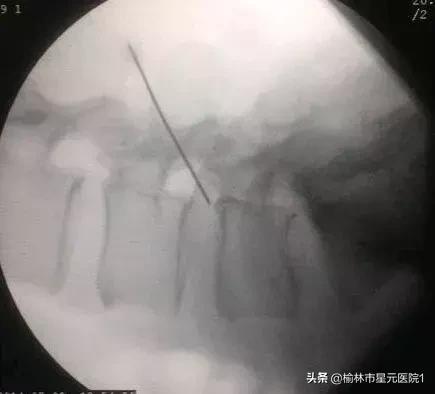

术前定位

术后创口7mm